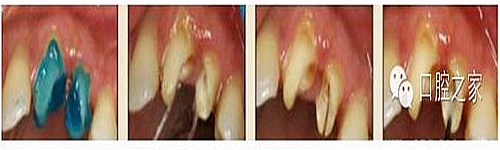

大多數(shù)醫(yī)生在樁道預(yù)備時習(xí)慣于干燥預(yù)備根管(圖 1),這樣很容易破壞根管壁的牙本質(zhì)結(jié)構(gòu),同時也可形成較厚的玷污層,影響樹脂水門汀與牙體組織的粘接。因此,臨床操作時應(yīng)選擇沖洗的方法冷卻預(yù)備根管(圖 2),防止牙膠及封閉劑粘連附著于根管壁形成第二玷污層(根管治療時形成的玷污層稱為第一玷污層),有利于樹脂水門汀與根管牙本質(zhì)的粘接。

圖1:干燥預(yù)備根管。

圖2:沖洗預(yù)備根管。